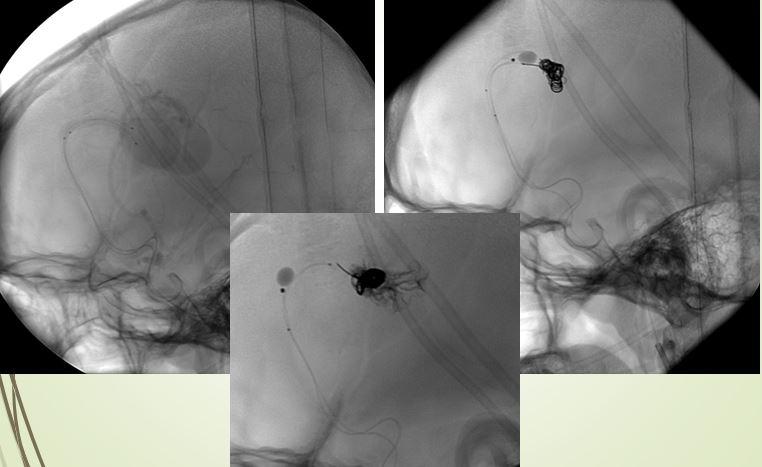

Sau tai nạn giao thông, bệnh nhân nam 34 tuổi bị đỏ mắt, lồi mắt, được chẩn đoán rò động mạch xoang hang và điều trị bằng phương pháp cổ điển là mổ động mạch cảnh, thả miếng cơ để bít lỗ rò.

H. Bệnh nhân nam 34 tuổi bị rò động mạch xoang hang sau tai nạn giao thông, tái phát sau mổ thả cơ và cột động mạch cảnh năm 2004

Phương pháp thả cơ được thực hiện khoảng năm 2007 trở về trước trong thời gian rất dài, vì các trường hợp rò động mạch xoang hang do tai nạn giao thông ở nước ta xảy ra rất nhiều, sau điều trị có trường hợp thành công, có trường hợp tái phát. Đây là trường hợp tái phát do phát sinh tuần hoàn bàng hệ, bệnh nhân vẫn còn đỏ mắt, lồi mắt. BS Cường cho biết tại thời điẻm 2004 cả nước gom lại chắc chưa được 10 cái coil, can thiệp đặt coil bệnh nhân sẽ tốn rất nhiều tiền.

Các bác sĩ có quyết định khá mạo hiểm là chọc trực tiếp vào động mạch cảnh ở cổ, sau đó can thiệp đặt bóng.

Ca can thiệp này khiến các bác sĩ vất vả vì phải ép động mạch cảnh suốt 1 giờ đồng hồ, đồng thời có bác sĩ tai mũi họng đứng bên cạnh, đề phòng tình huống phải mở khí quản.

Sau can thiệp, bệnh nhân đã được điều trị hiệu quả, sau can thiệp không để lại sẹo vết đáng kể.